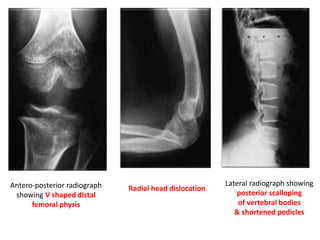

sandwich vertebrae /

rugger jersey appearance

increased density of osseous structures due to

accumulation of immature bone.

Generalized increased density of bones &

alternating areas of increased & decreased density

in metaphyses (bone-within-bone appearance).